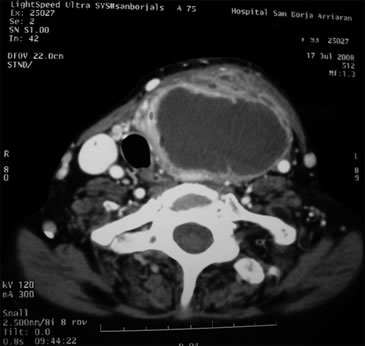

TAC cervical: Gran colección cervical izquierda en relación a lóbulo tiroideo ipsilateral extendiéndose hacia mediastino, con desviación de vía aérea (Figura 3).